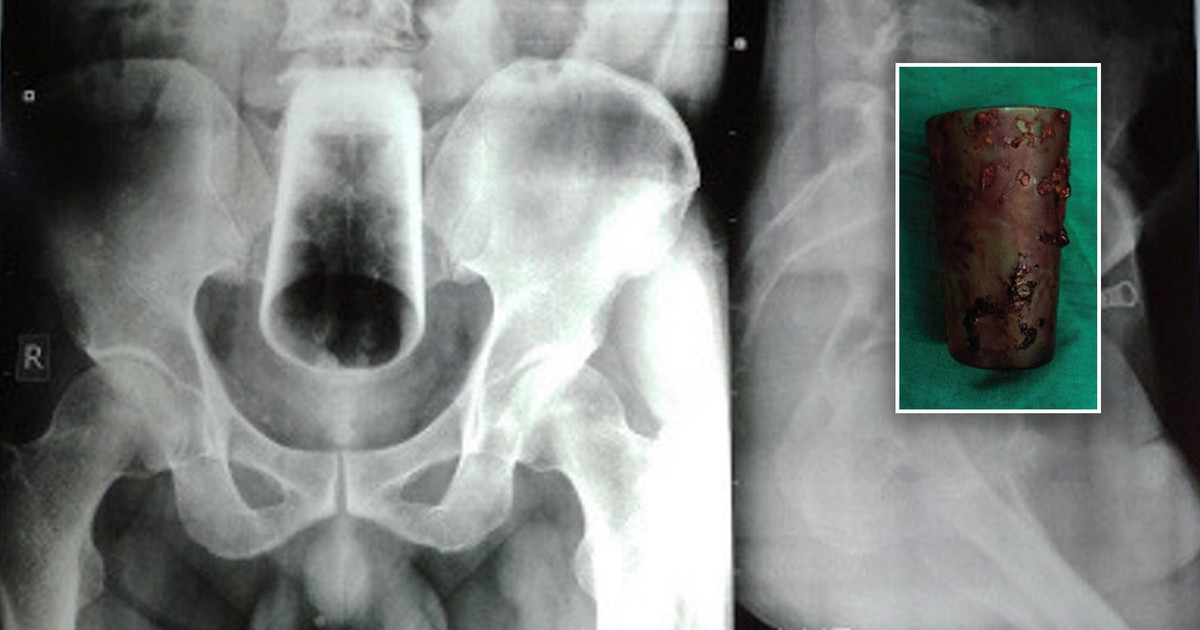

El caso del desafortunado nepalí se describe en el Journal of Nepal Medical Association. Este hombre de 47 años -y al parecer sin identificar- acudió al hospital porque hacía tres días que no defecaba. Inmediatamente quedó claro que la causa del estreñimiento era vaso de 12cmEstaba en su recto.

Desafortunadamente, el hombre lo volteó y el médico no pudo atrapar el vidrio deslizante. Tampoco pudo realizar una sigmoidoscopia no invasiva debido al riesgo de rotura del cristal.

El insaciable nepalí tuvo que operarse. Los médicos realizaron una enterotomía, es decir, una incisión en la pared intestinal. Gracias a esto, sacaron el vaso directamente del interior del hombre. Por supuesto, le tomaron una foto de inmediato.

El hombre rápidamente volvió en sí. Cinco días después de la operación, defecó solo y al día siguiente le quitaron el drenaje del fregadero. Después de siete días era como un recién nacido. Después de todo, Napalczyk admitió que en el momento del «experimento» estaba muy borracho. No se sabe cómo reaccionó su esposa ante la noticia de que su esposo estaba en el hospital.